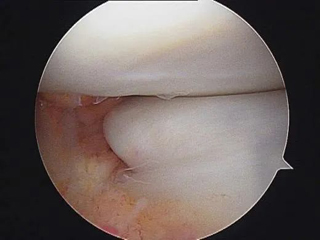

前交叉韧带损伤在儿童和青少年中越来越常见,损伤主要表现为两种形式:韧带实质部损伤和胫骨髁间棘撕脱骨折,团队经过20年的努力,已经将诊断及治疗流程标准化,目前正在科室行政主任杨征带领下承担北京市卫健委迎冬奥国际合作择优资助基金项目:中国儿童青少年前交叉韧带实质部损伤和胫骨髁间棘撕脱骨折诊疗指南的编写工作。

胫骨髁间嵴骨折